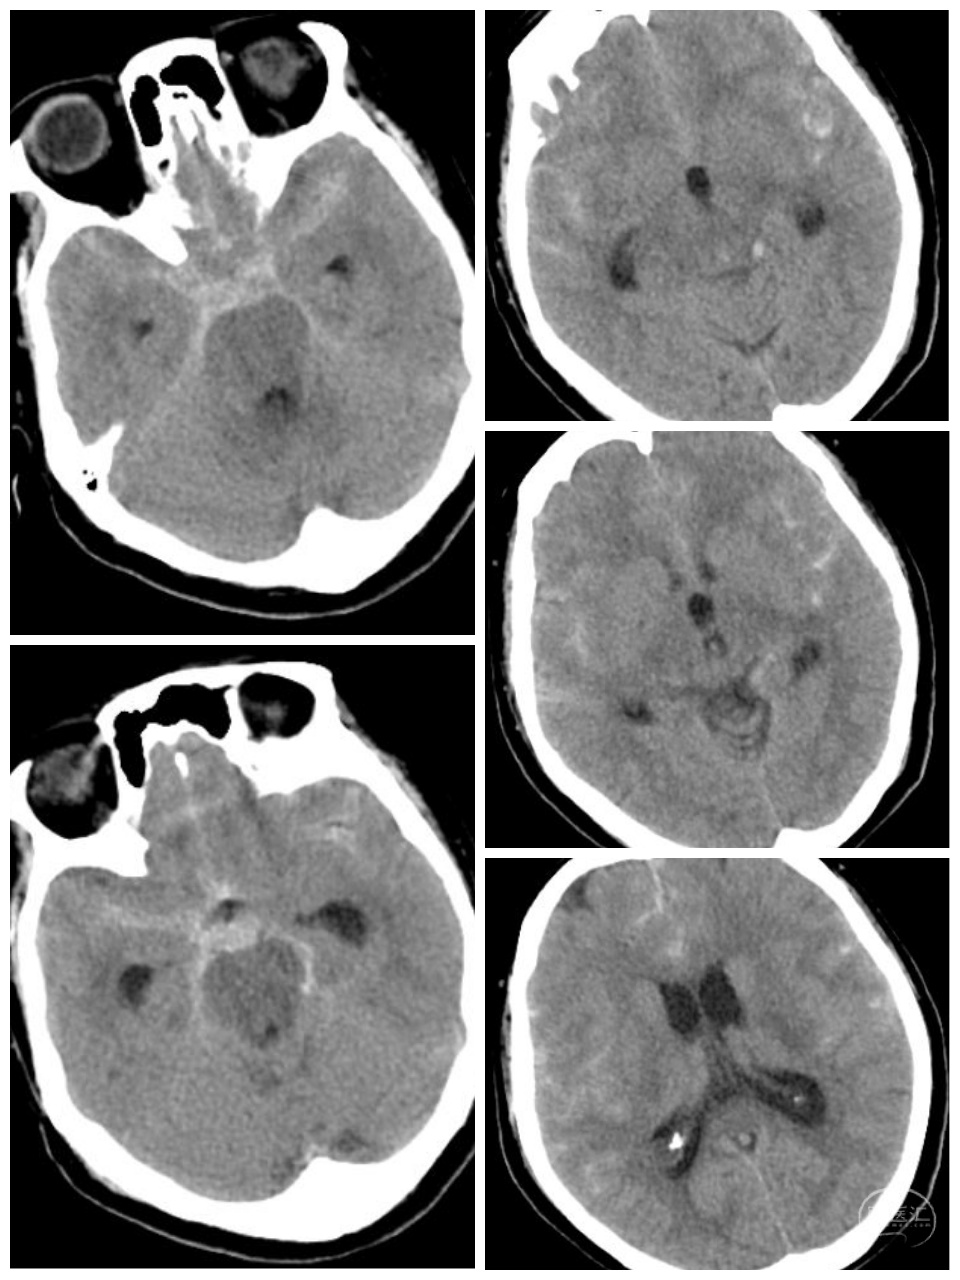

女性,66岁,突发剧烈头痛2小时。Hunt-Hess二级。

右侧颈内动脉-后交通动脉段分叶状动脉瘤。